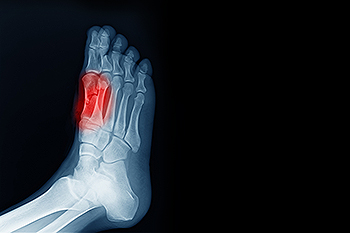

The underlying cause of ankle pain can be diagnosed by a chiropodist. Diagnoses are typically made based on your medical history, a physical examination of the affected ankle, and imaging studies such as X-rays.

A chiropodist can diagnose cuboid syndrome based on your medical history and a physical examination of the foot. Imaging studies, such as X-rays or MRIs, often fail to show the dislocated cuboid.